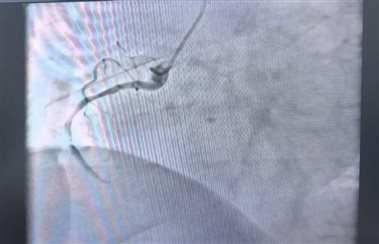

介入团队立即启动导管室。冠状动脉造影结果显示:患者右冠状动脉中段及远段95%以上狭窄,病情极为危重。医护团队紧密协作,迅速将导丝通过闭塞病变,经球囊扩张后,在病变处成功植入支架一枚,使患者心肌血液供应得以恢复,闭塞血管达到理想的TIMI血流3级状态。整个手术仅耗时30余分钟,术后患者症状显著缓解,生命体征平稳。